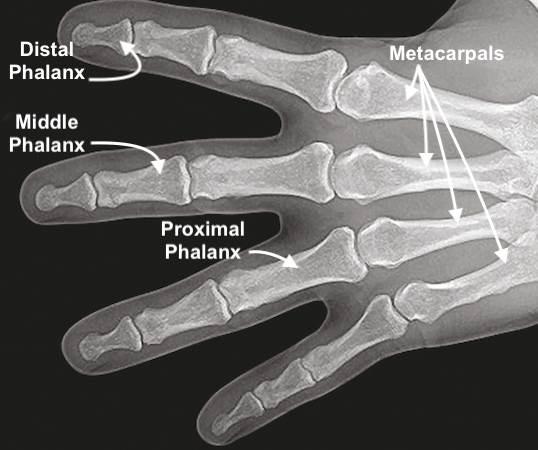

• X-ray showing the proximal phalanges of the hand.

X-ray showing the proximal phalanges of the hand.